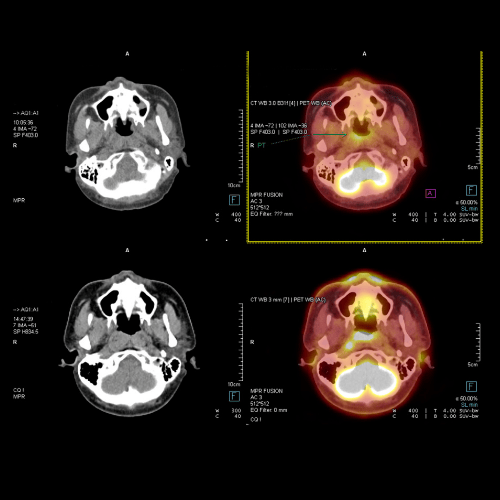

Nuclear medicine uses advanced imaging techniques to help detect cancer early and understand how the disease is affecting the body. PET-CT combines functional imaging with detailed diagnostic imaging, helping doctors identify cancer, evaluate its stage, and plan the right treatment approach.

PET-CT plays an important role in cancer screening and advanced cancer diagnosis for conditions like breast cancer, lung cancer, and colon cancer. It also helps monitor treatment progress and assess how well therapies such as chemotherapy or radiation are working. To better understand cancer care and diagnosis, visit our Understanding Cancer section.

PET-CT is a powerful imaging tool used to detect, diagnose, and monitor a wide range of conditions. In cancer care, it helps identify tumors early, determine the stage of disease, plan treatment, and assess how well therapy is working. Beyond oncology, PET-CT plays an important role in neurology by aiding in the diagnosis of various neurodegenerative disorders. In cardiology, it helps evaluate blood flow, detect heart muscle damage, and guide treatment decisions for heart disease.